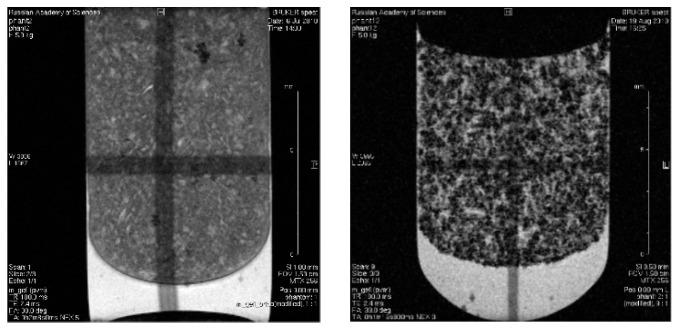

Type I interferons, particularly IFNα-2b, play essential roles in eliciting adaptive and innate immune responses, being implicated in the pathogenesis of various diseases, including cancer, and autoimmune and infectious diseases. Therefore, the development of a highly sensitive platform for analysis of either IFNα-2b or anti-IFNα-2b antibodies is of high importance to improve the diagnosis of various pathologies associated with the IFNα-2b disbalance. For evaluation of the anti-IFNα-2b antibody level, we have synthesized superparamagnetic iron oxide nanoparticles (SPIONs) coupled with the recombinant human IFNα-2b protein (SPIONs@IFNα-2b). Employing a magnetic relaxation switching assay (MRSw)-based nanosensor, we detected picomolar concentrations (0.36 pg/mL) of anti-INFα-2b antibodies. The high sensitivity of the real-time antibodies' detection was ensured by the specificity of immune responses and the maintenance of resonance conditions for water spins by choosing a high-frequency filling of short radio-frequency pulses of the generator. The formation of a complex of the SPIONs@IFNα-2b nanoparticles with the anti-INFα-2b antibodies led to a cascade process of the formation of nanoparticle clusters, which was further enhanced by exposure to a strong (7.1 T) homogenous magnetic field. Obtained magnetic conjugates exhibited high negative MR contrast-enhancing properties (as shown by NMR studies) that were also preserved when particles were administered in vivo. Thus, we observed a 1.2-fold decrease of the T2 relaxation time in the liver following administration of magnetic conjugates as compared to the control. In conclusion, the developed MRSw assay based on SPIONs@IFNα-2b nanoparticles represents an alternative immunological probe for the estimation of anti-IFNα-2b antibodies that could be further employed in clinical studies.

I 型干扰素,特别是 IFNα-2b,在引发适应性和先天免疫反应方面发挥着重要作用,与包括癌症、自身免疫和传染病在内的各种疾病的发病机制有关。因此,开发一种高度敏感的分析平台,用于分析 IFNα-2b 或抗 IFNα-2b 抗体,对于改善与 IFNα-2b 失衡相关的各种病理的诊断具有重要意义。为了评估抗 IFNα-2b 抗体水平,我们合成了超顺磁性氧化铁纳米粒子(SPIONs)与重组人 IFNα-2b 蛋白(SPIONs@IFNα-2b)偶联。我们采用基于磁共振弛豫切换检测(MRSw)的纳米传感器,检测出皮摩尔浓度(0.36 pg/mL)的抗-INFα-2b 抗体。通过选择高频填充短射频脉冲发生器,保证了免疫反应的特异性和水自旋的共振条件,实现了实时抗体检测的高灵敏度。SPIONs@IFNα-2b 纳米粒子与抗-INFα-2b 抗体形成复合物,导致纳米粒子簇的级联形成,进一步通过暴露于强(7.1 T)均匀磁场得到增强。所获得的磁性结合物表现出高的负磁共振对比增强特性(如 NMR 研究所示),当颗粒在体内给药时也得到保留。因此,与对照组相比,在给予磁性结合物后,我们观察到肝脏的 T2 弛豫时间降低了 1.2 倍。总之,基于 SPIONs@IFNα-2b 纳米粒子的开发的 MRSw 检测方法代表了一种替代免疫探针,用于估计抗 IFNα-2b 抗体,可进一步用于临床研究。